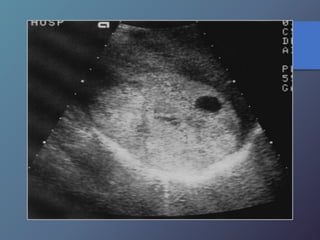

MT quísticas:

• Son poco frecuentes

• Son de paredes muy gruesas, presencia de

tabiques internos, ecos de nivel bajo.

• Pueden observarse en el cistadenocarcinoma

del ovario y del páncreas y en el carcinoma

mucinoso de colon.